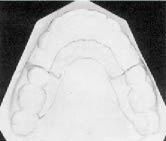

This appliance has no orthopedic effect, but it does accomplish what is required in the majority of extraction cases: it prevents treatment-induced mesial movement of maxillary posterior teeth without resorting to an extraoral appliance.

The palatal shelf anchorage device is a removable appliance that uses vertical surfaces of the hard palate for anchorage. The acrylic body of the appliance is adapted to these surfaces and to the teeth distal to the extraction sites. When anterior teeth are retracted, they are pitted against the "V"-shaped wedge of the appliance, which is being pressed into a similar "V"-shaped wedge formed by the lateral shelves of the hard palate.

This "V into V" anchorage is particularly efficient because the depth and form of the lateral shelves provide resistance to anterior molar movement, and the area is further increased by incorporating the anterior slope of the hard palate into the anchorage unit. Before the anchor teeth could move mesially, the whole device would have to move anteriorly and displace the entire hard palate mesially and laterally.

Unlike headgear, the appliance is inconspicuous and therefore acceptable to socially aware adolescents and adults. Reducible pontics in the extraction sites conceal the edentulous areas that would be visible until the extraction spaces are closed (Fig. 1). This esthetic feature is a powerful inducement for cooperation. I have found that when the appliance is broken or a pontic breaks away, the patient asks that it be replaced immediately. I want my patients to wear the appliance to alleviate the complications of lost anchorage. They want to wear it because they have been assured it will simplify treatment, and because it makes them less self-conscious after extractions are performed.

Fig. 1 Reducible pontics conceal extraction sites during retraction.

Fig. 3 Palatal shelf anchorage appliance outlined on cast, with clasps adapted against cervical margins and beneath heights of contour of second premolars. Only vertical slopes of palate are covered with acrylic; appliance does not butt against incisors.